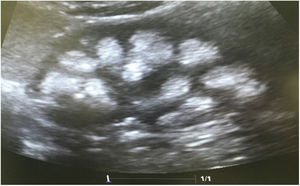

Case reportsCase 1This was a female patient aged four years three months. Birth weight 2800 g, length 48 cm and Apgar 8/9. History of craving for water and salt. Polyuria and nocturia as an infant. She was hospitalised 11 times for fever with no obvious focus. At the age of 20 months, she was diagnosed with herpes zoster and treated with aciclovir for seven days; subsequently, she developed diarrhoea, moderate dehydration and general flaccidity with the inability to walk. She was admitted to the Hospital General de Zona with suspected Guillain-Barré syndrome; weight 9.5 kg and height 82 cm (both in the 10th percentile). She was found to have hypokalaemia (2.5 mEq/l) and metabolic acidosis. After being started on intravenous treatment and the correction of her fluid/electrolyte imbalance, her strength improved and she was able to walk. However, the hyperchloraemic metabolic acidosis persisted. The clinical chemistry data are shown in Table 2 and the ultrasound findings in Fig. 2. A hearing test showed no evidence of sensorineural hearing loss. Her ophthalmological examination was normal. A urinary acidification test with sodium bicarbonate and acetazolamide was performed according to a previously described protocol (maximum urinary pCO2 test).11–13 The test was without complications, well tolerated and considered valid when bicarbonaturia greater than 80 mEq/l was found. A maximum urinary pCO2 of 80 mmHg was measured at 60 min (abnormal <70 mmHg) (Table 3). The patient was found to be a carrier of the same mutation as her mother. After three years of treatment with alkalis, her weight and height have improved (16.5 kg [47th percentile] and 103 cm [34th percentile], respectively). She is currently on treatment with potassium citrate (4.5 mEq/kg/day) and her hypercalciuria has remitted. Her blood pressure (BP) is normal (89/59 mmHg).